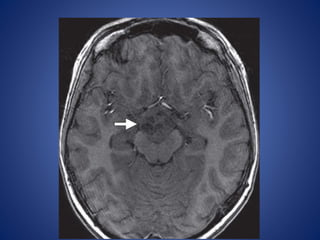

• #12 Pedunculated hypothalamic hamartoma in a 7-year-old girl with thelarche. (a) Sagittal T1WI shows a small, homogeneous, well-delineated round mass (arrowhead) that is isointense relative to gray matter and projects from the hypothalamus.

• #13 the mass (arrowhead) demonstrates no enhancement.

• #14 coronal T2-weighted MR image, the mass (arrowhead) is isointense relative to gray matter